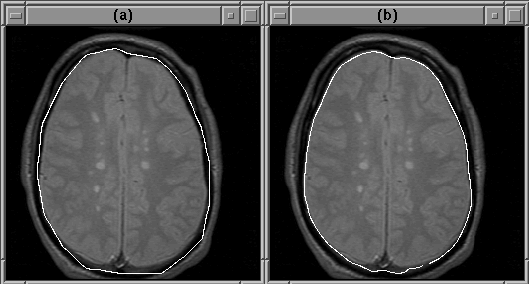

5.3.4 Contribution of Balloon Force

The balloon force contributes significantly to the accurate convergence of the active contour model algorithm when the initial guess is far from the object boundary. Figure 5.13 illustrates this contribution.

Figure 5.13: The balloon force enables the active contour model algorithm to find the intracranial boundary when the initial guess is poor. (a) Initial guess. (b) Final contour with balloon force disabled. (c) Final contour using balloon force.

Given an initial contour well inside the brain, the active contour model algorithm easily finds the intracranial boundary using balloon force. When the balloon force is disabled, the final contour attaches itself to detail inside the brain.